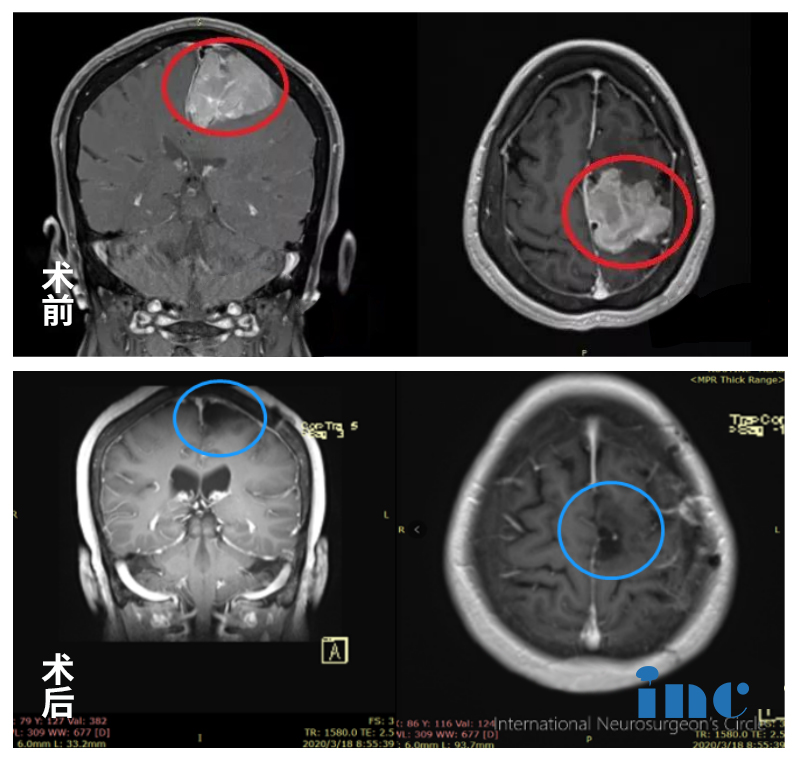

4、矢狀竇旁腦膜瘤

簡(jiǎn)要病史:王阿姨,退休老師,2012年就檢查出有“左側(cè)額部大腦鐮旁腦膜瘤”,由于腫瘤不到3cm加上無(wú)癥狀,前沿行了保守治療。2018年復(fù)查,腦膜瘤已大于5cm,逐漸出現(xiàn)肢體無(wú)力,復(fù)查MR顯示腫瘤侵犯靜脈竇、壓迫功能區(qū)。國(guó)內(nèi)各大醫(yī)院求診,均被告知手術(shù)難度大,腫瘤因?yàn)榭拷箪o脈竇難以全切,且腫瘤靠近運(yùn)動(dòng)功能區(qū),術(shù)后癱瘓可能較大(60-全切不等)

INC國(guó)際教授遠(yuǎn)程評(píng)估意見(jiàn):由于王阿姨年事已高,家人努力要幫她尋求有把握的專(zhuān)家來(lái)做手術(shù)。后通過(guò)INC國(guó)際神經(jīng)外科遠(yuǎn)程咨詢(xún)德國(guó)巴特朗菲教授咨詢(xún)意見(jiàn)。教授回復(fù)——手術(shù)可以全切,可以保留矢狀竇及相鄰靜脈,中央前回可以而且需保留,手術(shù)風(fēng)險(xiǎn)可以規(guī)避,可能不需要術(shù)后放化療。

矢狀竇旁腦膜瘤——腦瘤治療案例圖

INC國(guó)際教授主刀手術(shù)后:腫瘤全切、矢狀竇成功重建、運(yùn)動(dòng)功能區(qū)無(wú)損傷。術(shù)后當(dāng)天即拔插管,術(shù)后1天遷出ICU,術(shù)后2天可以在護(hù)理人員攙扶下走路康復(fù)訓(xùn)練,術(shù)后5天已經(jīng)可以獨(dú)自走路,無(wú)需陪同,肢體肌力明顯好轉(zhuǎn),術(shù)后1周+,恢復(fù)地和正常人一樣,精神狀態(tài)很好。術(shù)后1年半,復(fù)查MR發(fā)現(xiàn)沒(méi)有腫瘤殘余,術(shù)前肢體無(wú)力明顯好轉(zhuǎn),也無(wú)手術(shù)后遺癥的產(chǎn)生。巴教授建議2-3年再次復(fù)查MRI。